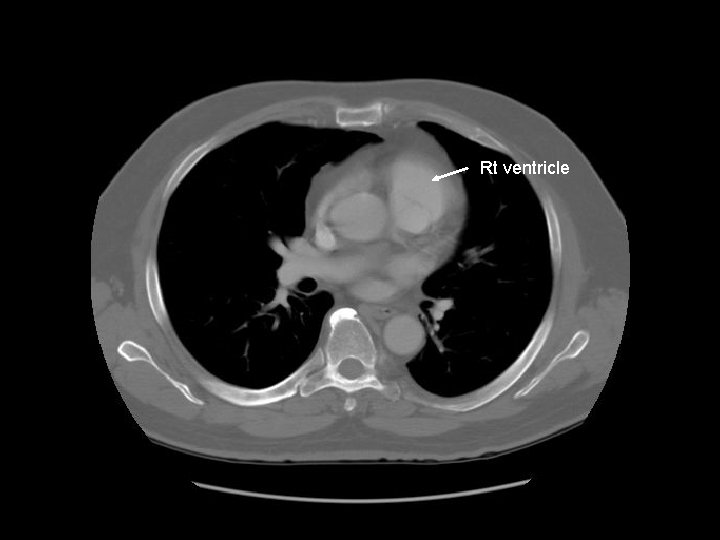

Rt ventricle